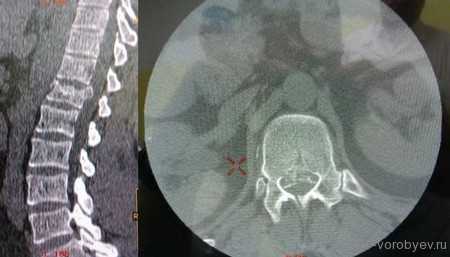

На данных томограммах представлен нестабильный перелом тела Тн12 позвонка

Первым этапом выполнена ламинэктомия с транспедикулярной фиксацией китайской системой, а затем проведена корпорэктомия, корпородез аутокостью и тораколюмбальной пластиной китайского производства.

Пациент с неспецифическим спондилодисцитом в грудном отделе позвоночника

Выполнена операция торакотомия, трансплевральная корпорэктомия, комбинированный корпородез аутокостью и пластиной Centaur фирмы Stryker